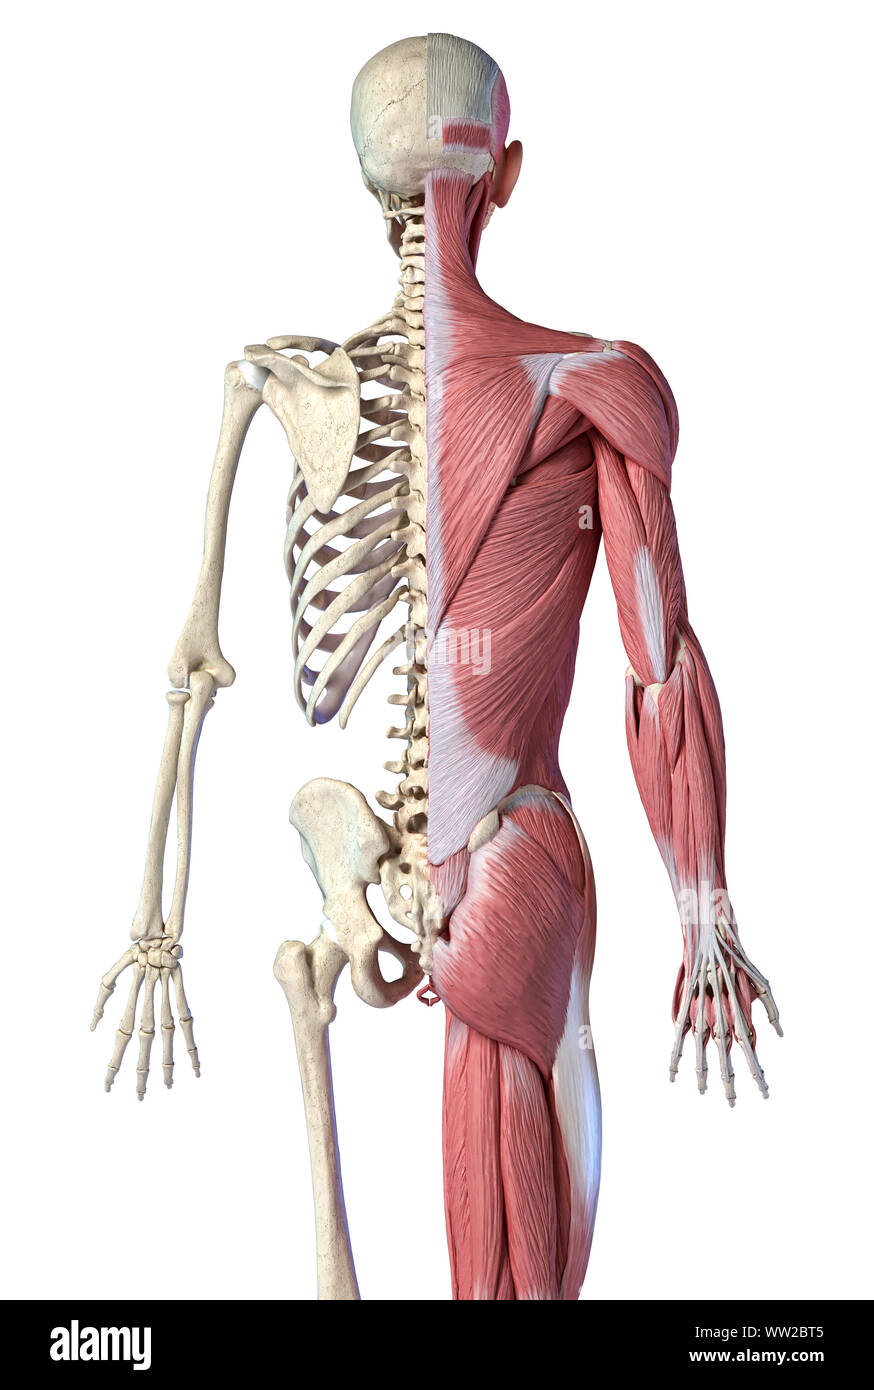

RFWW2BT5–Die männliche Anatomie, 3/4 Abbildung Muskel- und Skeletterkrankungen Systeme, Rückansicht auf weißem Hintergrund. 3D-Anatomie Illustration.